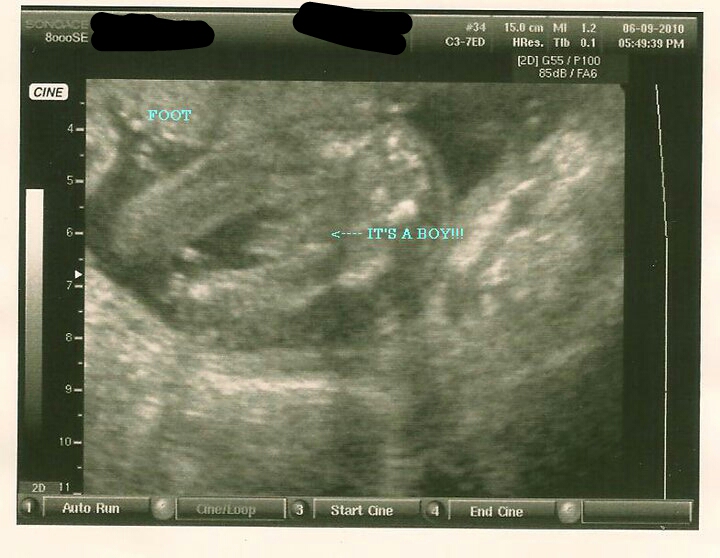

Suppose to be a potty shot of the scrotum but it looks weird to me too as my first sons was completely different Attachment 1817 this is my first sons and CLEARLY you can tell he he's a boy